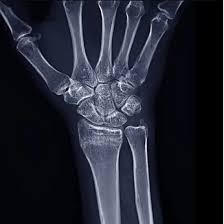

X-ray of Right Wrist AP & Lateral Views

Are you seeking an affordable Right Wrist X-ray (AP and Lateral views)? Medifyhome provides low-cost diagnostic imaging with high-quality results, working with NABL and NABH-accredited diagnostic centers to provide accurate and reliable results. This X-ray is traditionally employed to detect wrist fractures, dislocations, arthritis, infection, and other ailments. It provides distinct images from various directions, enabling practitioners to more accurately evaluate and manage pain, swelling, trauma, and post-operative healing. The procedure is quick, pain-free, and painless, rendering it a superior diagnostic tool for wrist ailments. To schedule a low-cost Right Wrist X-ray (AP and Lateral Views), visit Medifyhome or call +91 9100907036 +91 9100907622.

An X-ray of the Right Wrist (AP and Lateral Views) is a diagnostic procedure that uses numerous angles to diagnose fractures, dislocations, arthritis, and other abnormalities. It is a quick, painless, and non-surgical evaluation that allows for exact diagnosis and treatment planning.

An X-ray of the Right Wrist AP & Lateral Views can detect fractures, dislocations, joint arthritis, bone infections, and signs of bone tumors or cysts. It also helps assess bone alignment and soft tissue swelling around the wrist.